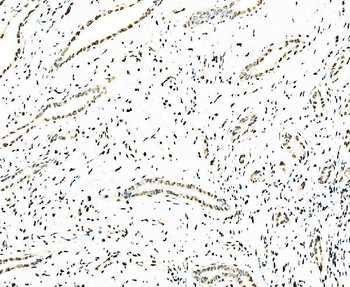

50 μl, 100 μl - Featured

ICC, IF, IHC-Fr, IHC-P, WB

Human, Mouse, Rat

Zebrafish

Rabbit

Recombinant

Unconjugated

50 μl, 100 μl, 25 μl - Anti-KIFC1 Antibody [orb865535]